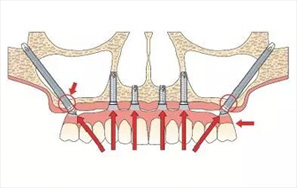

“穿颧种植术”是一种通过颧骨固定种植牙,将种植体植入到位于人面中部前,眼眶的外下方呈菱形较硬的骨头——颧骨,被种植牙界誉为“珠穆朗玛峰”的顶级技术,俗称“无土栽培术”

“穿颧种植术”受力效果好,稳定性强,可避免或减少术中大量植骨的风险,适用于上颌骨切除、上颌骨严重萎缩,常规内外提升也无法达到种植条件的无牙颌患者......查看详情